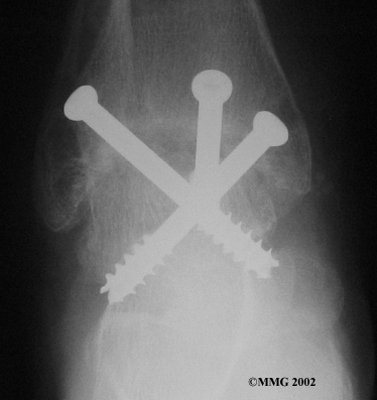

It is important when the surfaces are removed that the angles of the cut surfaces are correct. When the tibia is brought against the talus, the foot should be at a right angle to the lower leg. Once the cuts are made the bones must be held in place while they fuse. This can be done using large metal screws and metal plates if necessary. The screws are usually under the skin and are not removed unless they begin to rub and cause pain.

Inserting the screws

After ankle fusion, the physical therapists at FYZICAL North Port can help you learn to walk smoothly and without a limp. Although time needed for recovery varies among patients, an ankle brace will typically replace your cast after eight to 12 weeks. Your surgeon will take X-rays frequently to see if the bones are fusing together. You will probably need to use crutches during the time you wear the cast. As the fusion grows stronger, you will begin to put more weight on your foot when walking.